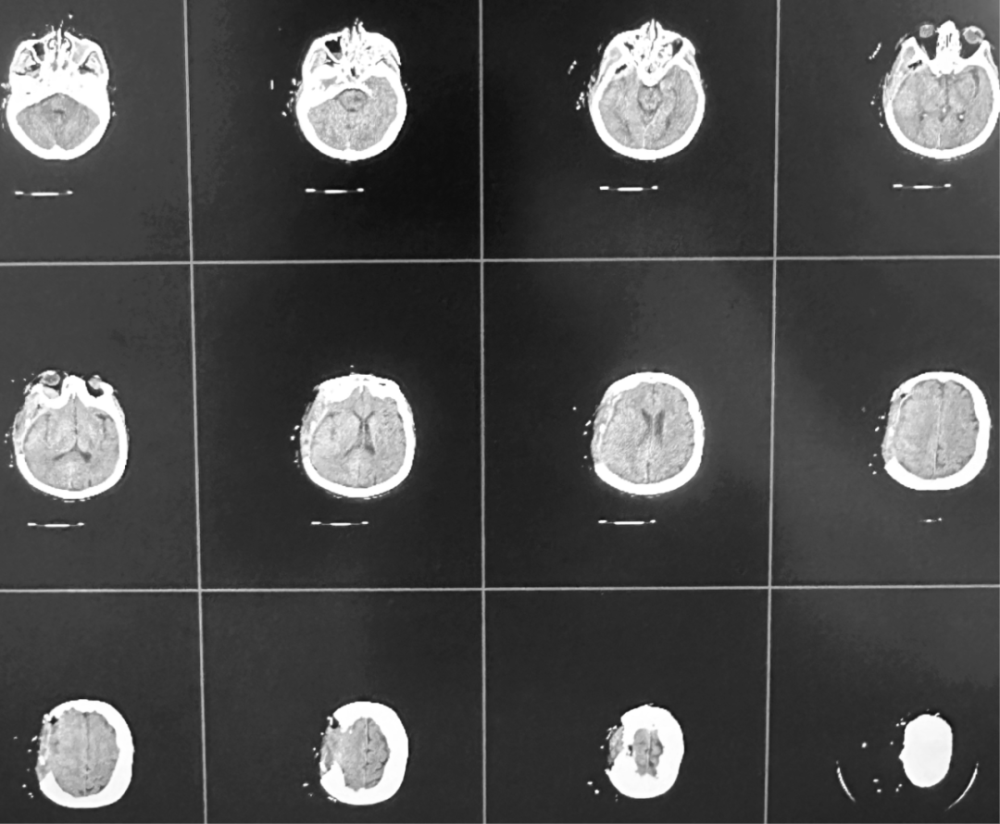

术后影像

手术前一天,刘鹏程主任医师在复合手术室内为患者施行肿瘤供血动脉部分栓塞术,为后续肿瘤切除奠定基础。次日,由王宁教授主刀,在麻醉团队全程护航及手术团队通力配合下,历经数小时,成功将侵犯颅内外及颅骨的巨大肿瘤完整切除。手术在彻底清除肿瘤的同时,最大程度保护了患者的正常神经功能,实现了功能保留与根治性切除的双重目标。术后患者生命体征平稳,未出现任何神经功能新增损伤,目前正在顺利康复中。